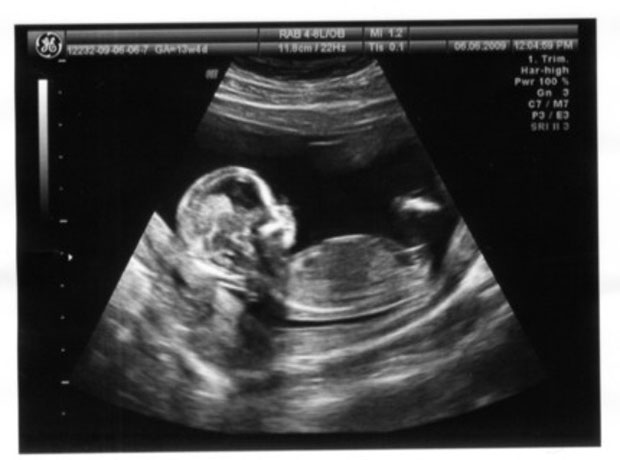

Первый скрининг, или скрининг 1 триместра – это комплексное исследование, которое призвано выявить патологии развития плода.

Состоит оно из двух этапов – сдачи крови из вены и УЗИ.

Последнее кстати, может быть как трансвагинальным (когда датчик вводится во влагалище), так и абдоминальным (когда врач осматривает плод через кожу живота).

На каком сроке проводится это исследование? В идеале на 11-13 неделях беременности, когда все органы и системы плода сформированы.